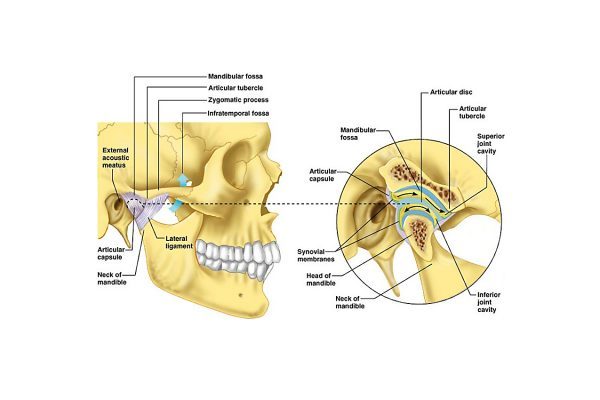

- Oclusão e ATM: estudo e tratamento da dor oro-facial; de problemas oclusais e da articulação temporo-mandibular;